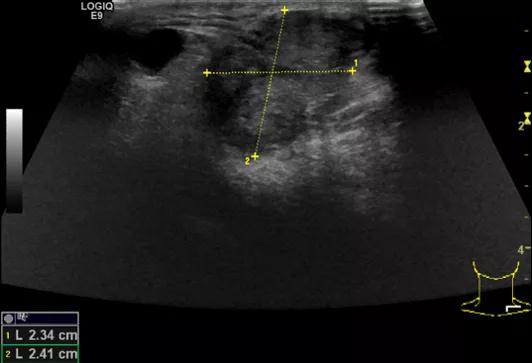

第三例是甲状腺癌患者,双侧甲状腺癌切除术后、碘治疗后一年余效果欠佳,超声显示左颈3区3枚低回声结节,穿刺示甲状腺乳头状癌转移。患者不愿意手术,希望采取局部治疗。对病灶进行液体隔离后采取热消融术,由于淋巴结较小,热消融一分钟左右完全灭活,术后增强影像显示没有脏器充填。

(病例3图例)